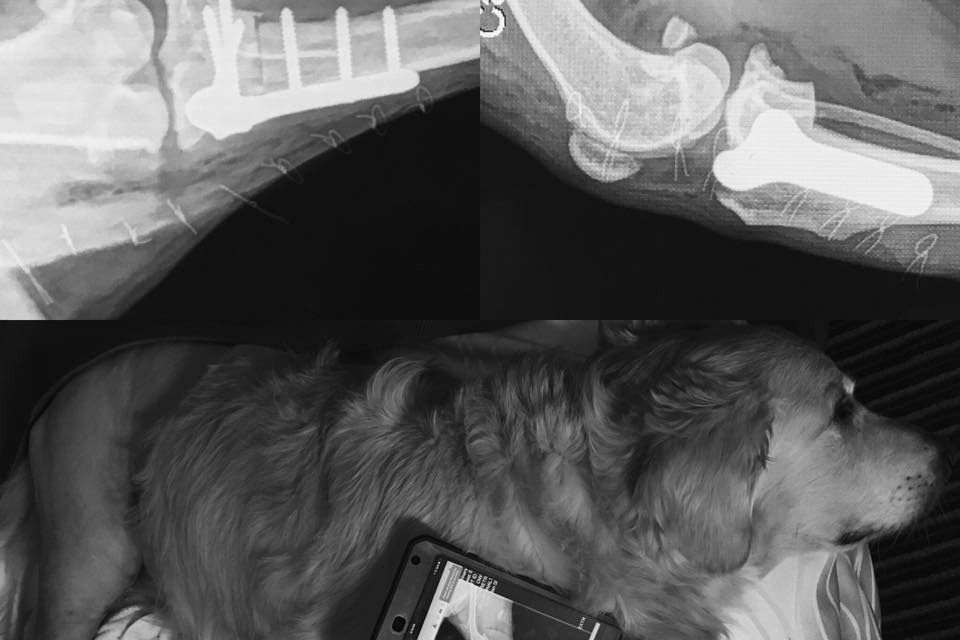

Meet Samson, a beautiful 12 y/o Golden Retriever with a charismatic personality was adopted 4-years ago and trained as a psychiatric service dog (PSD) for reducing hyper-vigilance through teamwork for his owner.

In October of 2017, Samson suffered from his first ACL tear in his right knee, resulting in a need for TPLO surgery to reconstruct and stabilize his right knee in January of 2018, recovering in April 2018.

On Saturday, April 28th, Samson tore his other ACL in the left knee while camping in the Sequoia National Forrest and will require the same TPLO surgery. Tearing both ACL's is common for retrievers his age.